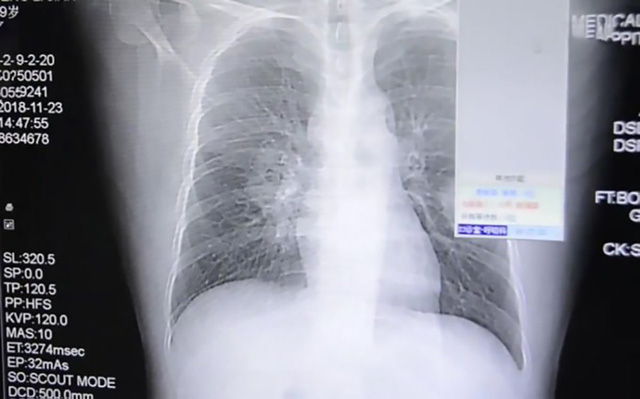

Phổi của bệnh nhân tên Peng bị nhiễm nấm phổi.

Các bác sĩ nghi ngờ Peng bị viêm phổi, nhưng sau khi sử dụng mọi biện pháp không hiệu quả, các bác sĩ đã tiếp tục làm các xét nhiệm và khẳng định Peng bị nhiễm nấm ở trong phổi.

Mọi chuyện chỉ được làm rõ khi Peng kể lại thói quen kì dị của mình. Việc ngửi tất bẩn mỗi ngày chính là nguyên nhân khiến Peng hít phải bào tử nấm.